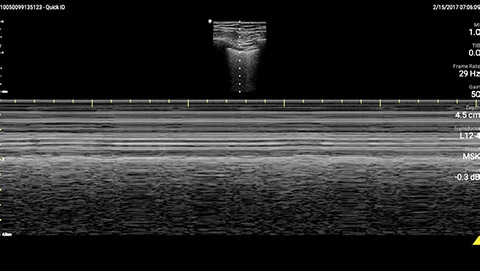

The patient had reduced LV systolic function without new or severe valvular pathology, a dilated, non-collapsing IVC, and diffuse B lines (left greater than right) on lung ultrasound imaging.

M-mode demonstrating lung sliding

Inferior vena cave